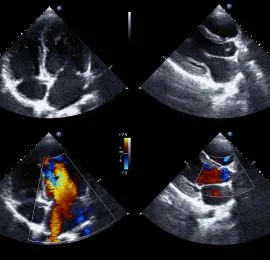

2D Echocardiography

Ultrasound-based imaging test to evaluate heart structure, function, and detect abnormalities in real time.